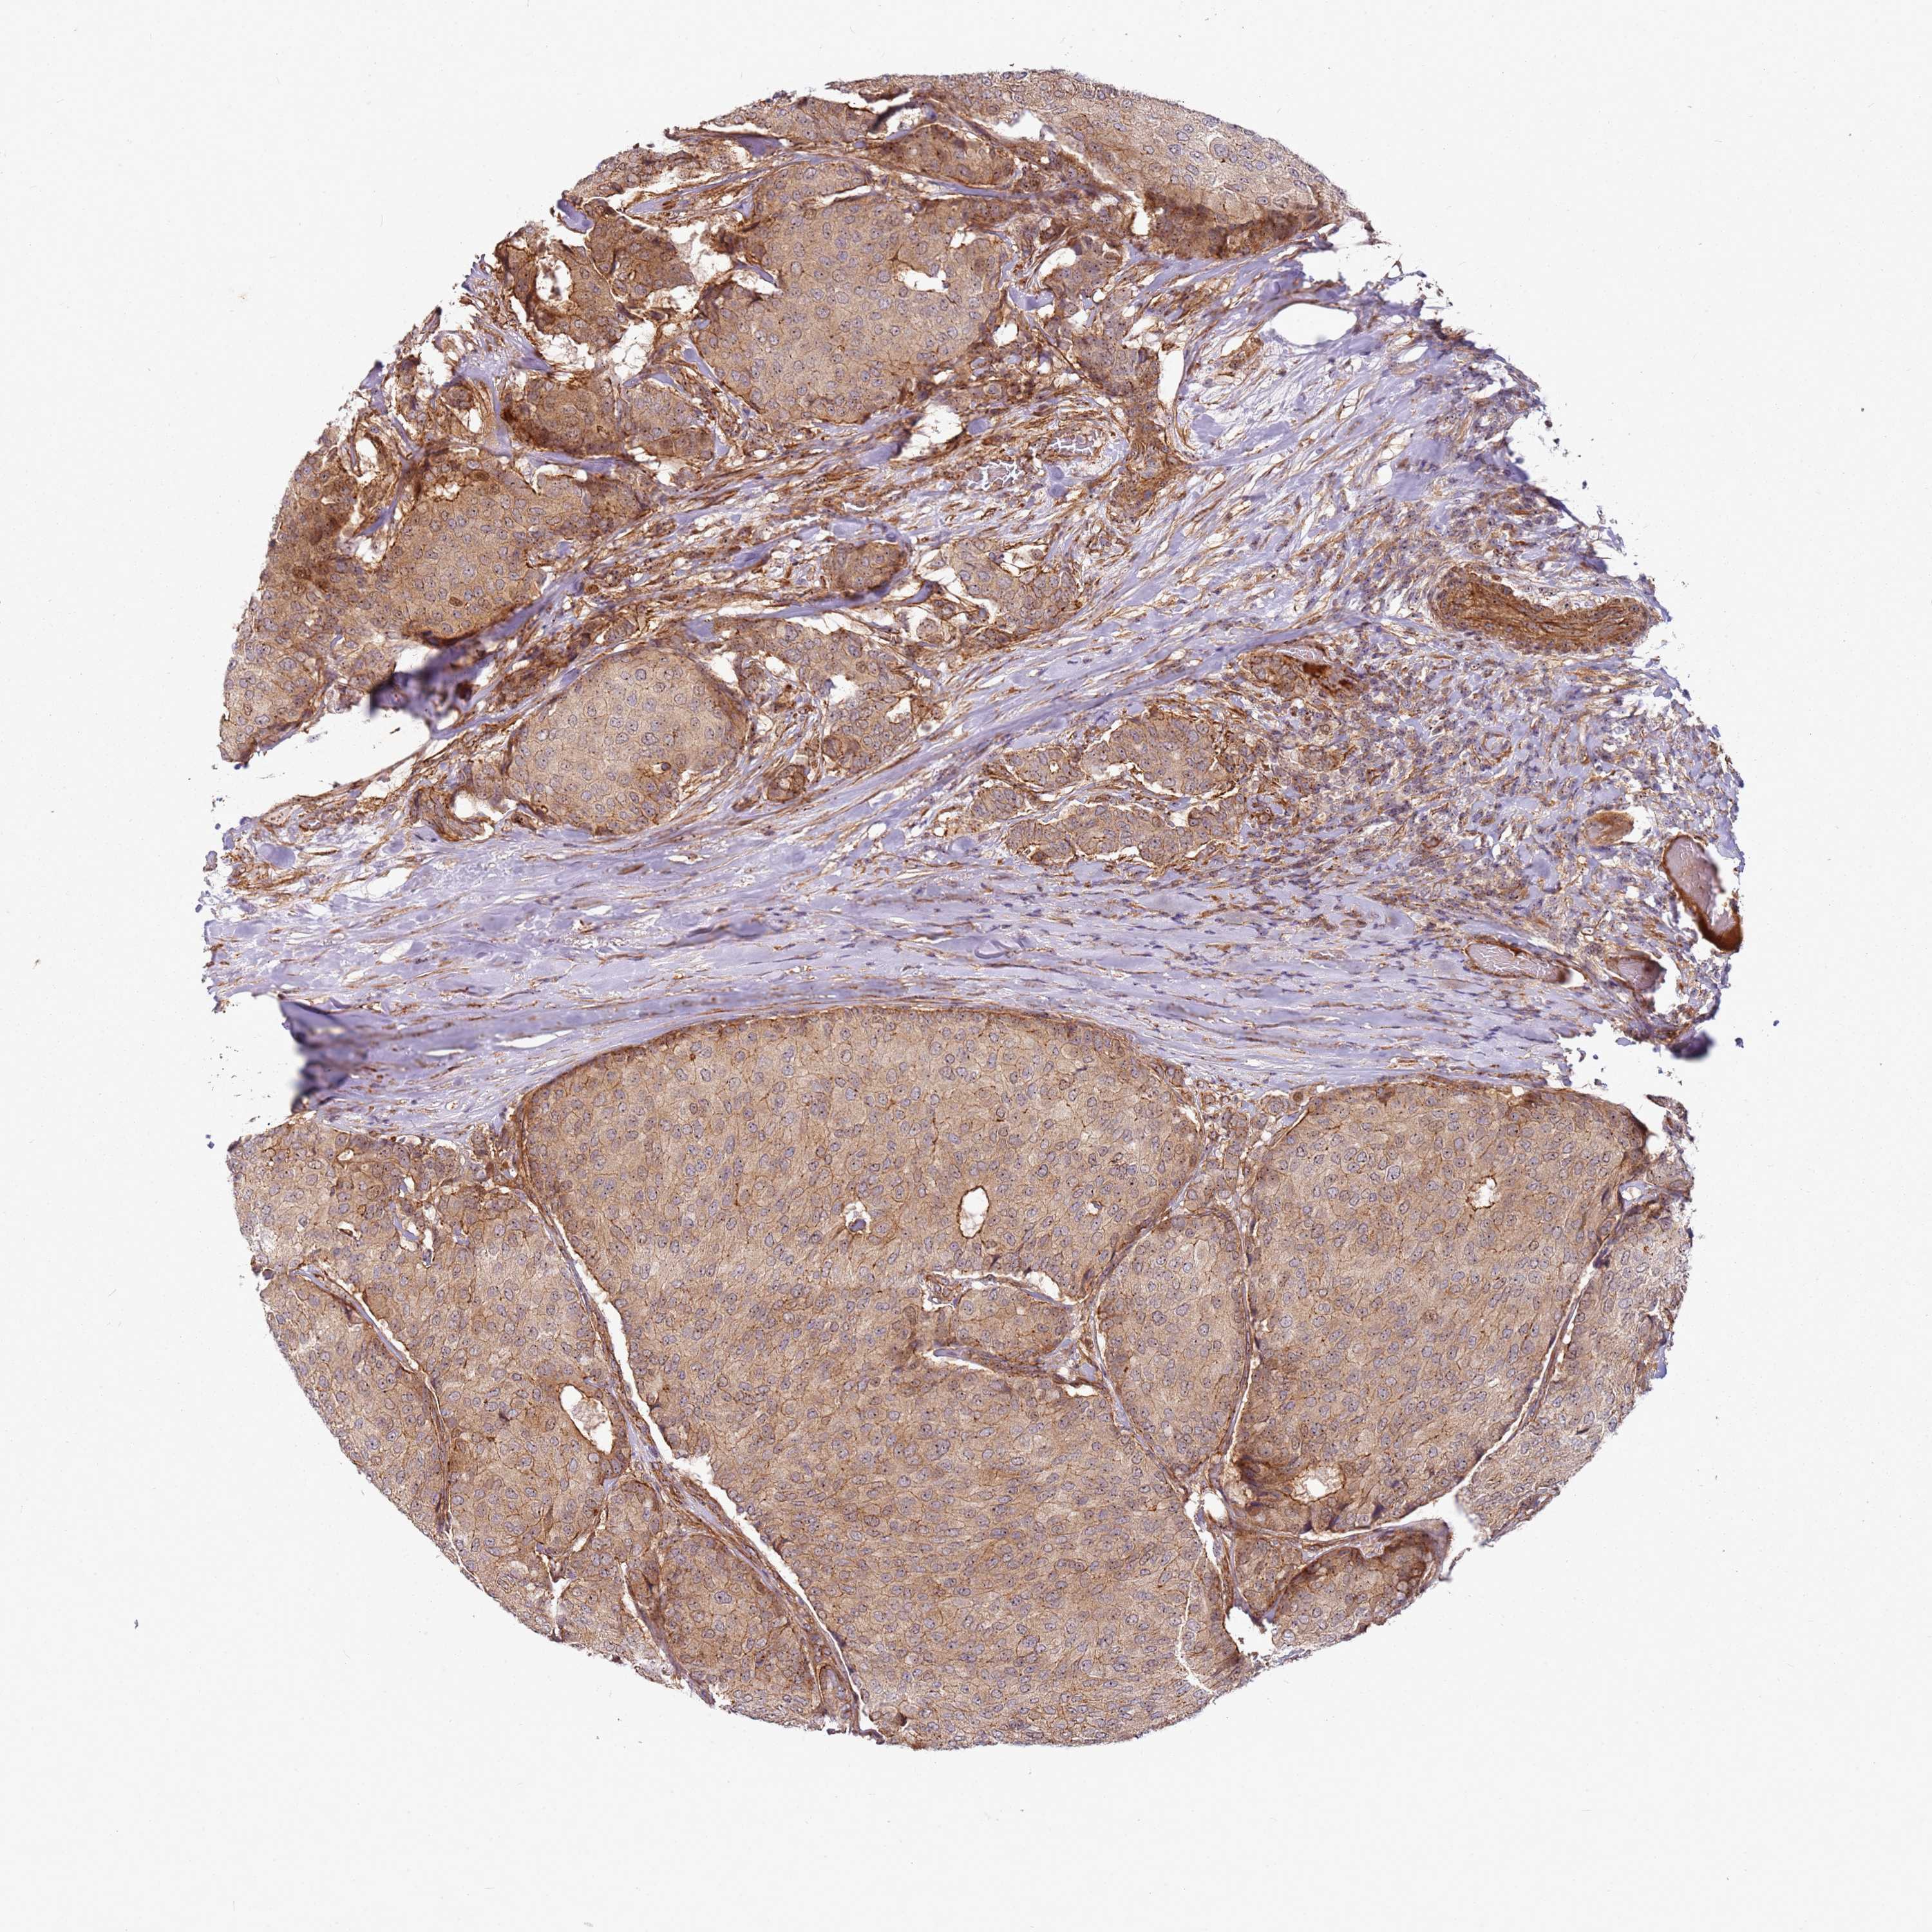

CANCER BREAST CANCER Show tissue menu

BRCA TCGA BRCA VALIDATION PROTEIN EXPRESSION